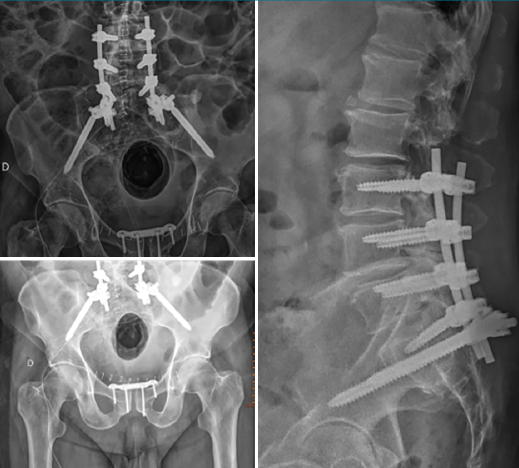

Figura 5. Control radiológico postoperatorio.

Por cuestiones de estabilización del estado general del paciente, así como logísticas, se difirió la cirugía definitiva 16 días, siendo los tiempos medios descritos en la literatura de 8,6 días(4). Dado el tipo de fractura de nuestro paciente, planteamos una fijación lumbopélvica desde L3 sin tornillos iliosacros asociados, dado que el desplazamiento y el cuerpo vertebral de S1 no lo permitían. El hecho de subir un nivel por encima de L4 es porque el pedículo de L5 derecho se encontraba afectado por la fractura, no permitiendo un buen anclaje del tornillo pedicular. No practicamos ningún tipo de maniobra de reducción debido a que el paciente no presentaba clínica neurológica y, dado que inicialmente presentó radiculopatía S1, el riesgo de reproducirla en las maniobras de reducción era elevado. La lesión del anillo anterior pélvico se intervino mediante reducción abierta y fijación con una placa en la sínfisis púbica (Figuras 4 y 5).